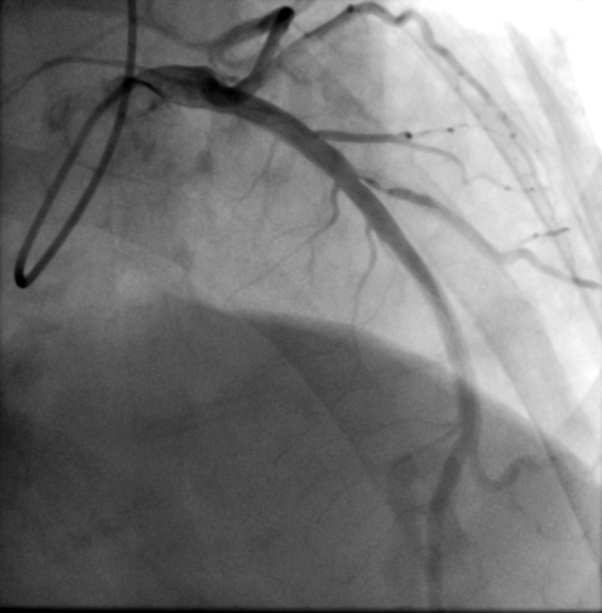

Diagnostic coronary angiogram breakdown as follow:Left Main: NormalLeft circumflex & Right coronary artery: Mild diseaseLeft anterior descending: NormalDiagonal branch (D2): Sizable vessel with severe 90% stenosis from ostium to proximal part with heavy calcification